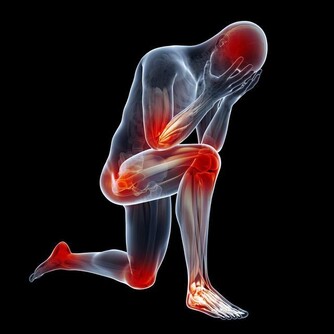

如果你出現持續背痛或者經常感覺不舒服,以及經常感覺疲倦,你也可能面臨維生素D缺乏的風險。蛀牙、脫髮或慢性肌肉疼痛也可能是維生素D缺乏的警示信號。經常頭痛的人也有維生素D缺乏的風險,這一症狀常常被人們所忽略。